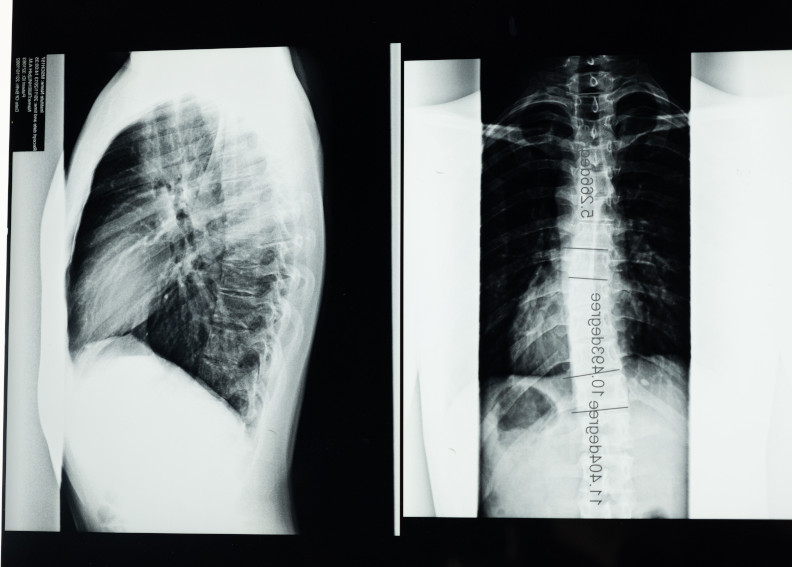

Il trattamento della scoliosi

Cos’è la scoliosi e come si tratta? La ginnastica correttiva e la ginnastica posturale sono un valido contributo.

La scoliosi nella fase evolutiva: una cattiva compagna

La scoliosi è ancora poco conosciuta e non ci sono miracoli per risolverla… ma la ginnastica posturale e correttiva può aiutare.